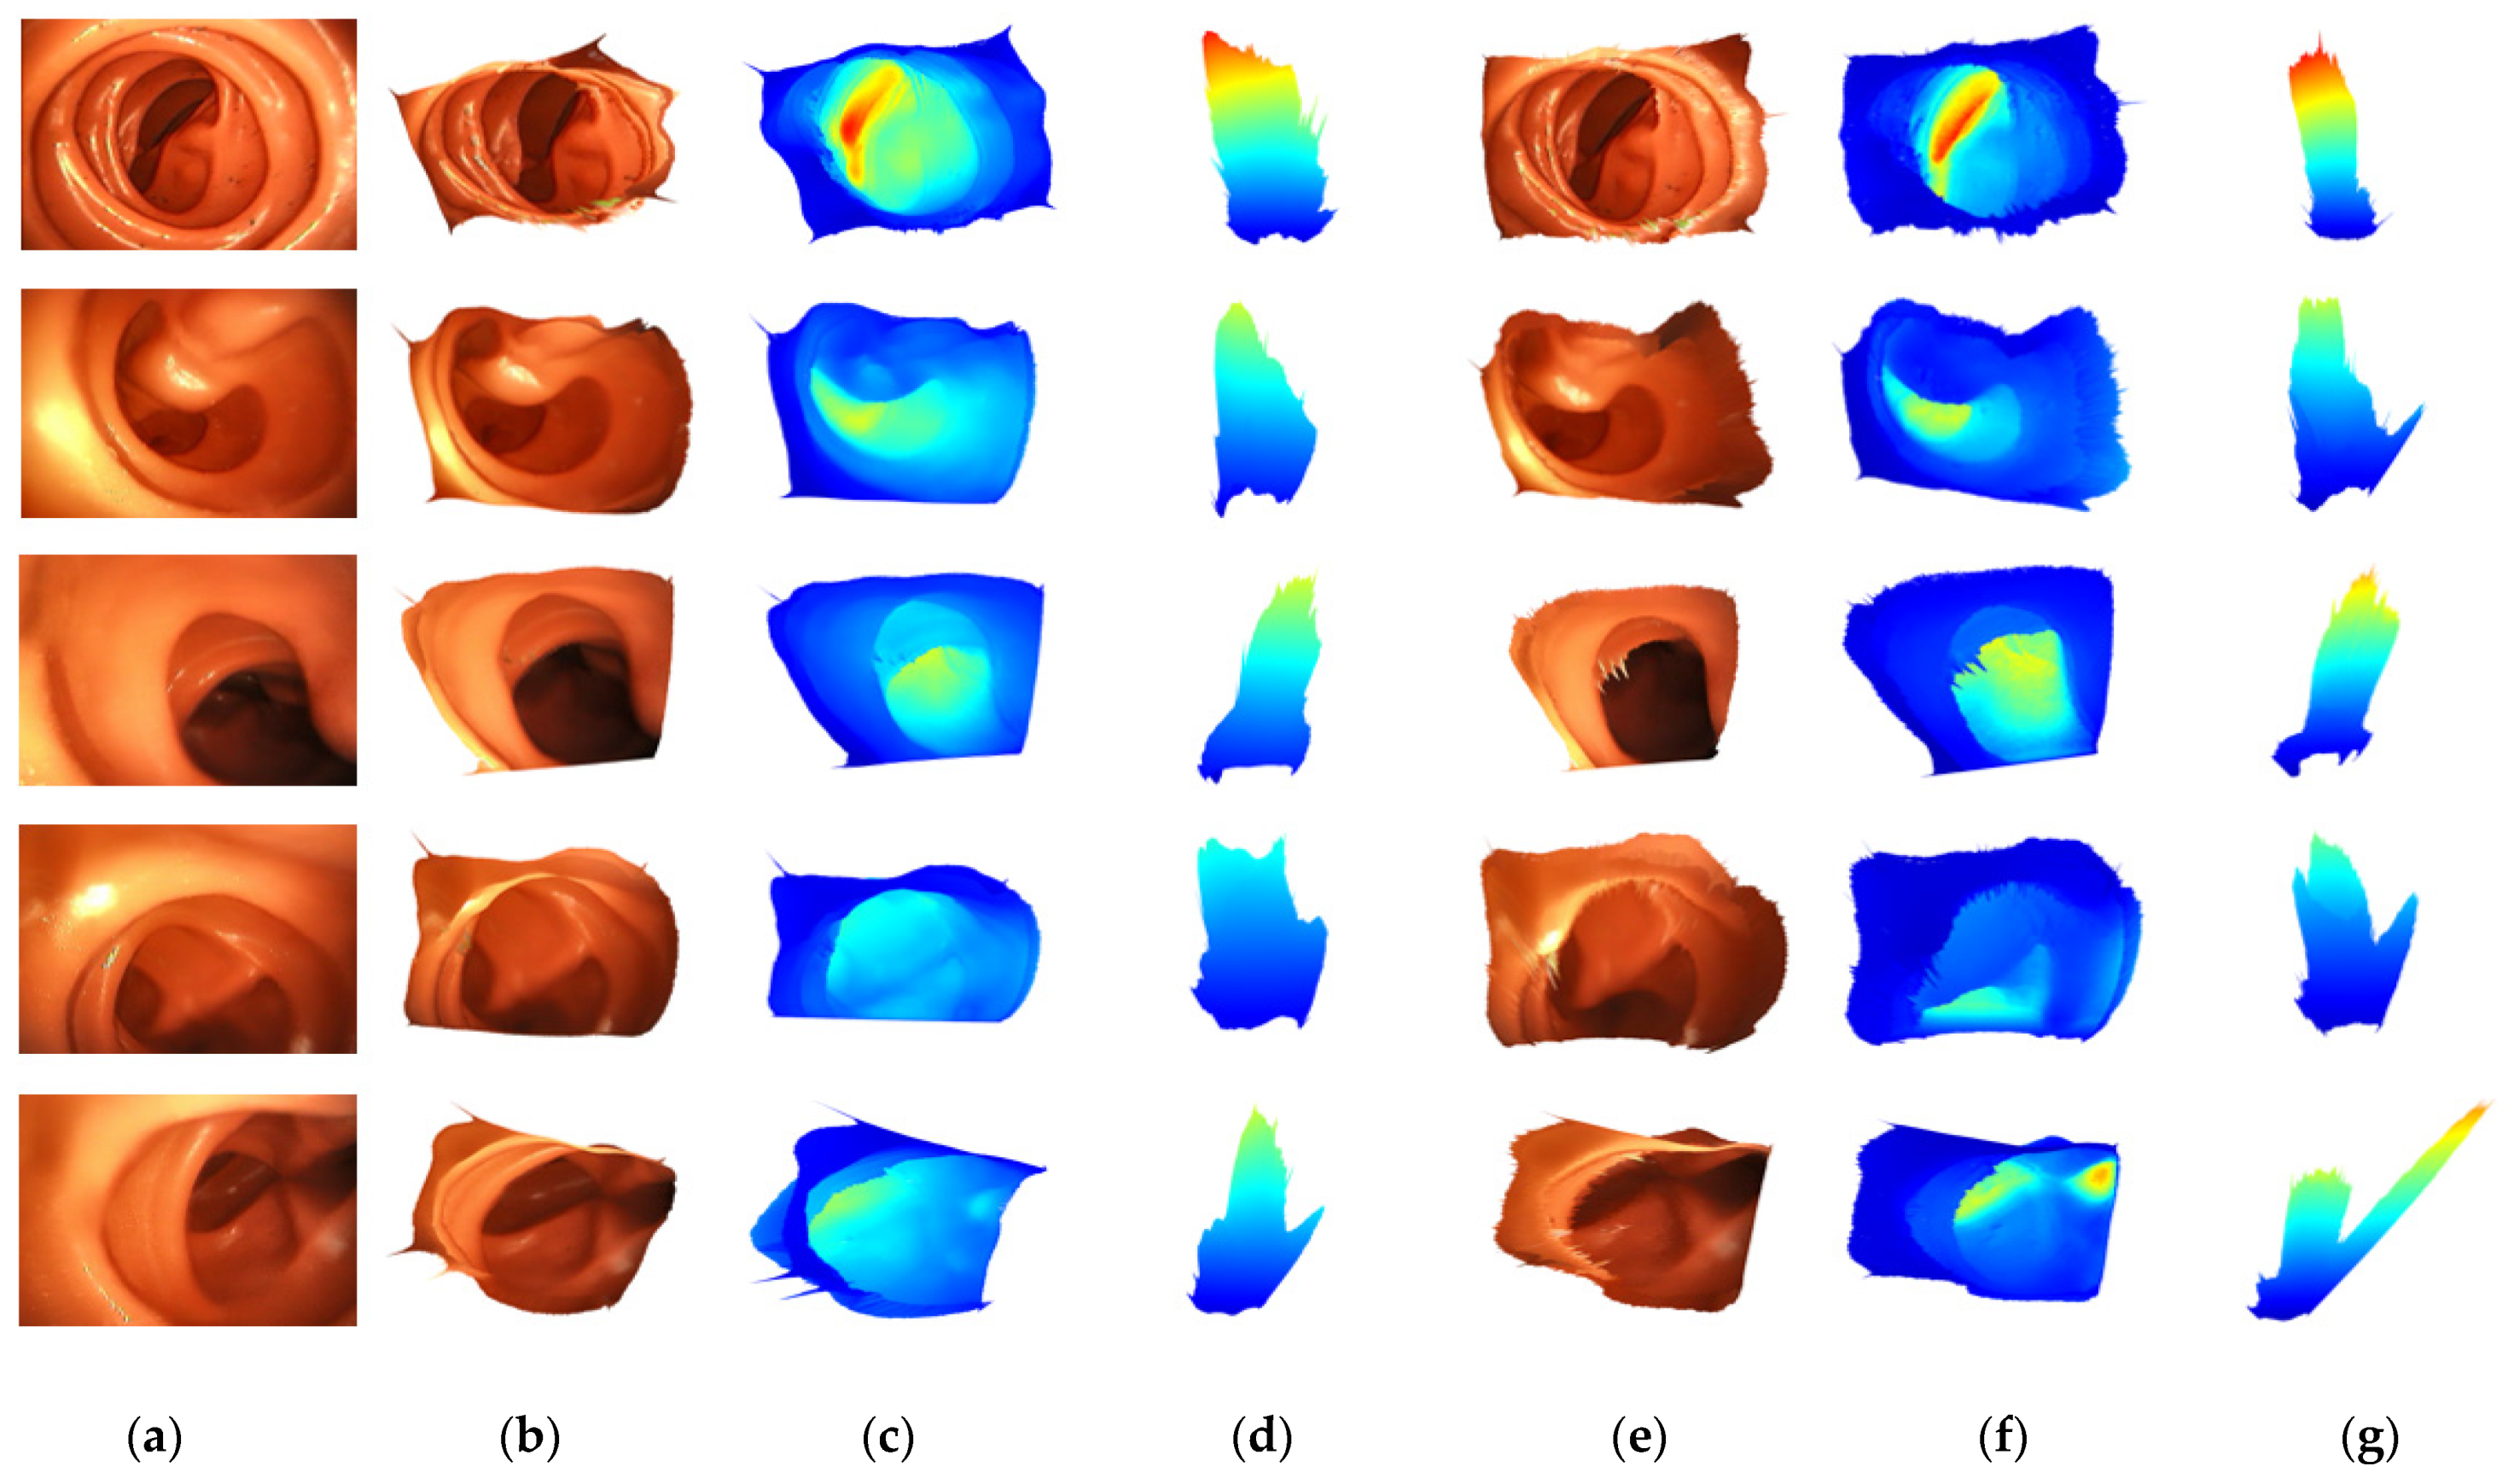

2.1. Colonoscpy Depth Estimation

4.3. Ablation Study

5. Discussion